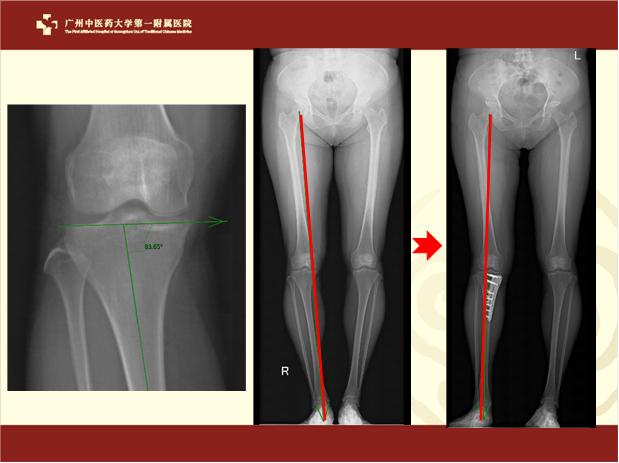

图二 胫骨高位截骨术前后x片。

图二中,术前x片显示膝关节内侧狭窄,小腿(胫骨)内翻;术后膝关节中心向外侧转移,小腿(胫骨)内翻得到纠正。